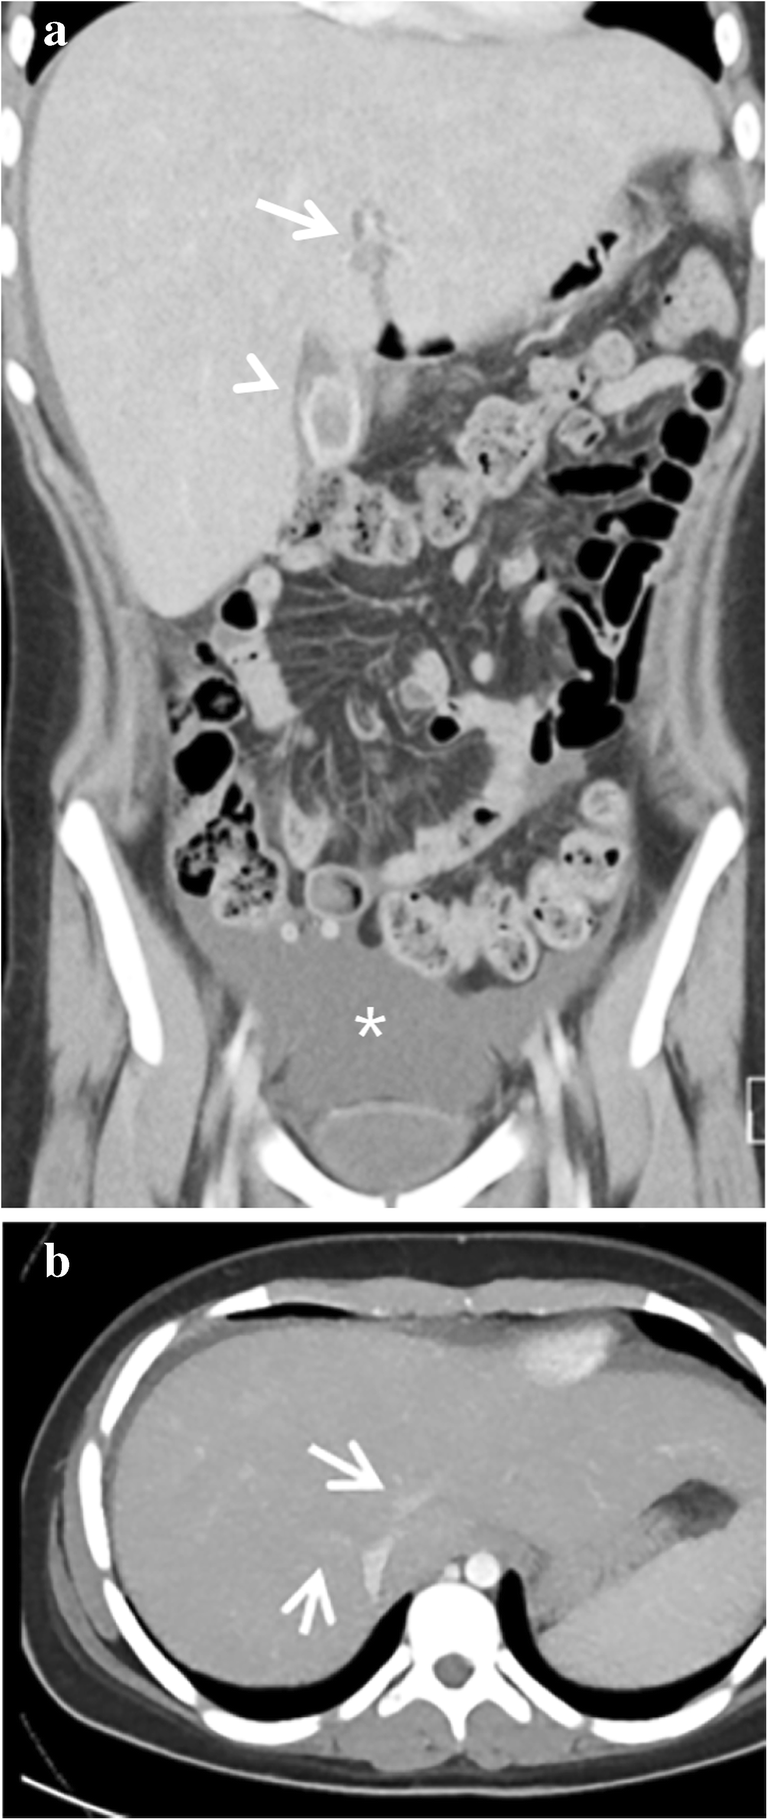

Due to radiation exposure, CT is not the imaging modality of choice for evaluating sinusoidal obstruction syndrome in children. Signs of sinusoidal obstruction syndrome can, however, be a coincidental finding when a CT is performed for a different indication. As with US, ascites, hepatomegaly, periportal edema, gallbladder wall thickening, hepatic vein narrowing, widening of the hepatic artery and the formation of collaterals can be recognized on CT. In addition, heterogeneous hypo-attenuation of liver parenchyma and patchy enhancement have been described (Fig. 5). In a recent meta-analysis, the latter two features with or without narrowing or invisible hepatic veins in the portal equilibrium phase were shown to be the most important CT features for diagnosing sinusoidal obstruction syndrome in adults [29].

Fig. 5

Computed tomography (CT) features of sinusoidal obstruction syndrome. A CT scan in a 14-year-old girl (same patient as in Fig. 1c) with stage 4 neuroblastoma was performed a month after high-dose busulfan/melphalan and autologous stem cell transplantation. She had a history of gallstones. She presented with nausea, right upper quadrant pain and elevated C-reactive protein. a A coronal contrast-enhanced abdominal CT shows enlarged liver, periportal edema (arrow), gallbladder wall thickening (arrowhead) and ascites (asterisk). b A transverse abdominal contrast-enhanced CT shows narrowing of the hepatic veins (arrows). The thickened gallbladder wall was initially interpreted as acute cholecystitis. However, the elevated bilirubin, elevated liver transaminases in combination with liver enlargement, ascites and a recent history of busulfan/melphalan chemotherapy and autologous stem cell transplantation were diagnostic for severe sinusoidal obstruction syndrome. This patient was treated conservatively at the time and recovered. She has not had symptomatic cholecystolithiasis or cholecystitis since